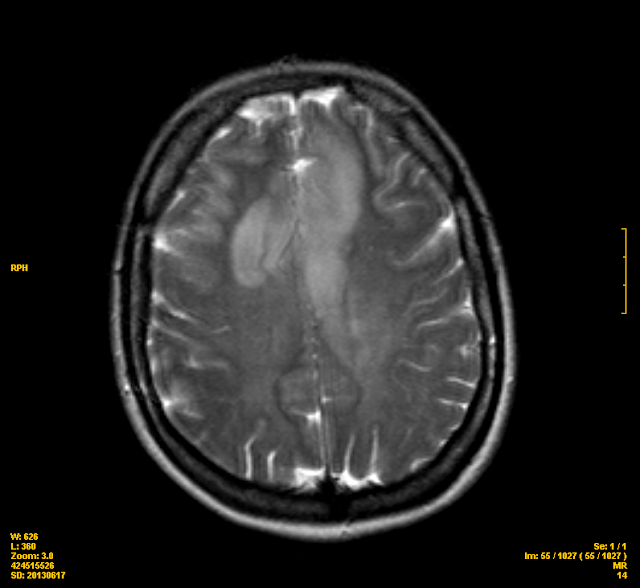

Gliomatosis cerebri is a rare growth pattern of some brain tumors, impacting at least three cerebral lobes, mostly with bilateral involvement of the cerebral hemispheres. It can be seen in some types of diffuse glioma, most notably glioblastoma. It consists of infiltrative threads that spread deeply into the brain, making them very difficult to remove with surgery or treat with radiation and is associated with poor prognosis.

As defined by the WHO, gliomatosis cerebri spans at least three cerebral lobes, usually involves both hemispheres and can also spread deeply into the gray matter or into infratentorial structures like the brainstem, cerebelleum or spinal cord.

Gliomatosis cerebri is most often caused by glioblastoma, but can also arise from astrocytoma, oligodendroglioma or other types of diffuse glioma. Other pathologies such as vasculitis, encephalitis or leukoencephalopathy may also cause similar radiological findings.